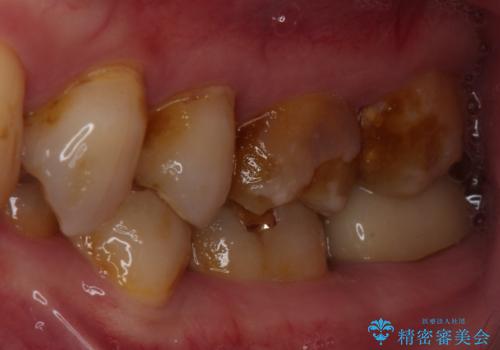

- 食事で堅いものを噛んだ時に歯が欠けてしまったとのことで来院された患者様です。

咬合面に大きな修復物が入っており、その境目から破折し、歯肉の内側の歯根にまで破折が及んでいました。